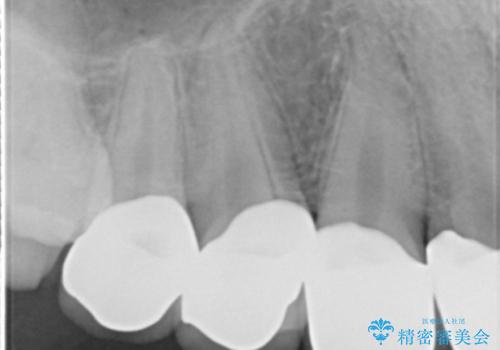

精査したところ、ほとんどの歯が保険内のレジンで充填されており、咬み合わせも悪く咬合していない歯もありました。

虫歯をしっかりと治療したのち、オールセラミッククラウンによる補綴治療を行いました。